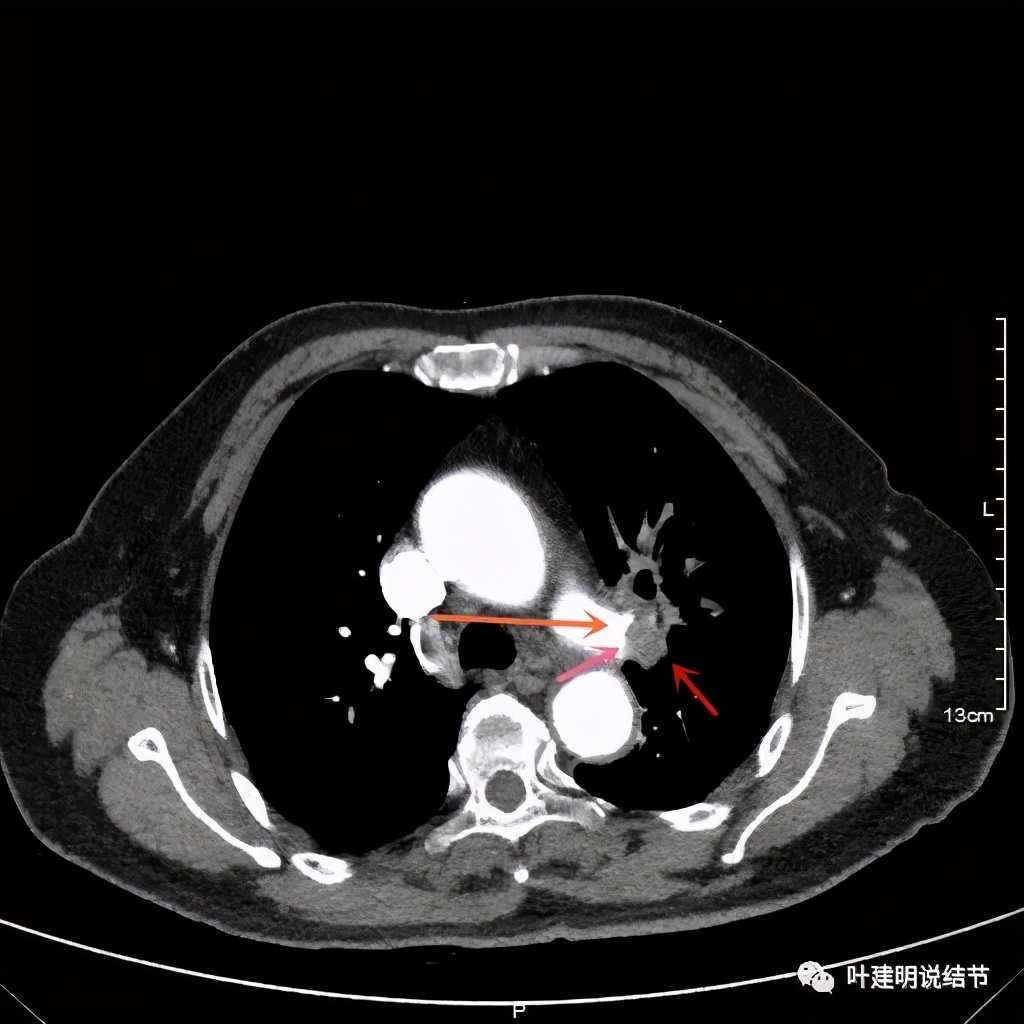

上图示肺动脉仍与软组织影关系密切,没有间隙可分开

上图示肺动脉与肿瘤的关系仍紧密

上两图示叶间肺动脉的上缘与肿瘤没有界限